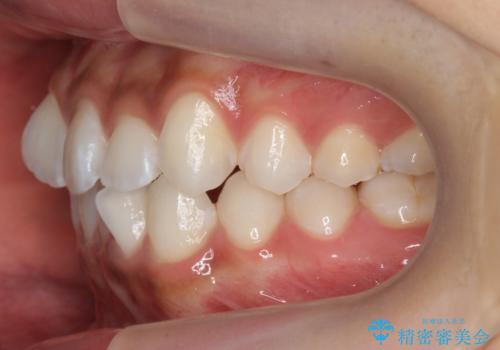

前歯のがたつき 1年かからず治療 マウスピース矯正

- 前歯のがたつきを主訴に来院。

インビザラインで歯を抜かずに並べました。

マウスピースの延長(リファインメント)もなく、短期間で綺麗に並びました。